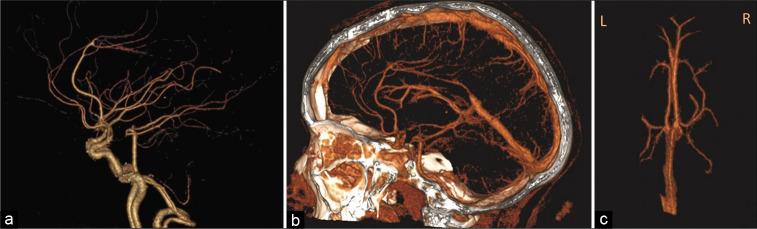

A 16-year-old girl presented with a 1-month history of gradual visual deterioration in the left eye, intermittent headache, and vomiting. Brain imaging showed hematoma located between the leaflets of the septum pellucidum with obstructive hydrocephalus. Transcallosal resection of interventricular mass was done. The patient was discharged with improved neurological symptoms; however, the left eye vision did not recover. Imaging demonstrated a unique anatomical variant in deep vascular structures.

一名16岁女孩,有1个月左眼视力逐渐下降、间歇性头痛及呕吐病史。脑部影像学检查显示血肿位于透明隔小叶之间并伴有梗阻性脑积水。行经胼胝体间脑室内肿物切除术。患者出院时神经症状改善;然而,左眼视力未恢复。影像学显示深部血管结构存在一种独特的解剖变异。